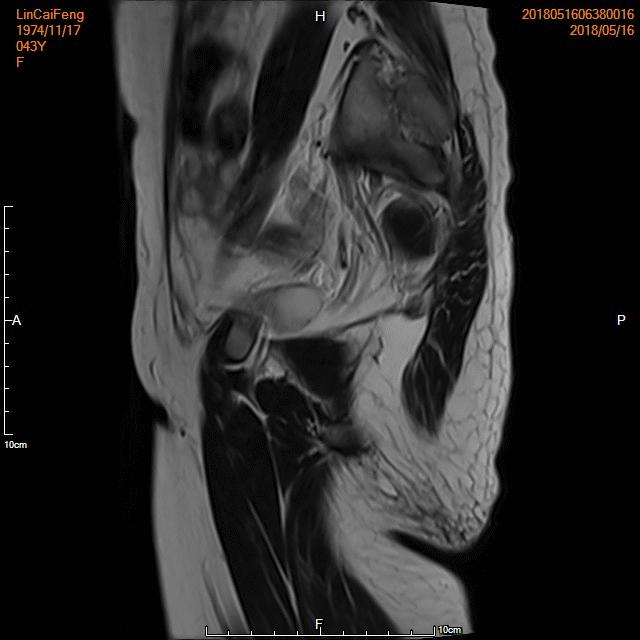

- 术前MRI显示子宫明显增大,病灶主要位于子宫前壁。

- 术后3个月复查MRI显示子宫明显缩小,前壁病灶萎缩坏死。

- 术前MRI检查显示子宫明显增大,弥漫型子宫腺肌症。

- 术后复查MRI显示子宫明显缩小,腺肌瘤明显坏死吸收。